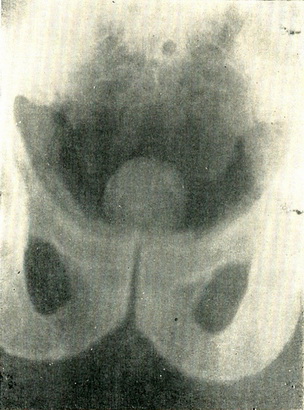

Діагностика в більшості випадків не складна. Вік хворих, типовий анамнез, повільне млявий розвиток хвороби, ощупываемая пальцем через пряму кишку безболісна пухлина рівномірно еластичної консистенції з гладкою поверхнею дозволяють легко поставити діагноз. Шляхом цистографії з киснем в прямій і напівбоковой проекції можна отримати зображення врізається в міхур аденоми, що є об'єктивним та документальним підтвердженням діагнозу (рис. 119).

Рис. 119. Пневмоцистограмма; на тлі заповнює сечовий міхур кисню над лонним зчленуванням видно тінь аденоми передміхурової залози.